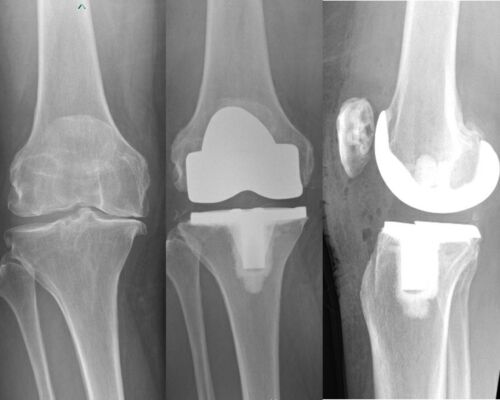

JOINT REPLACEMENT / ARTHOPLASTY

Advanced knee arthritis – left image,

Total knee replacement – right image